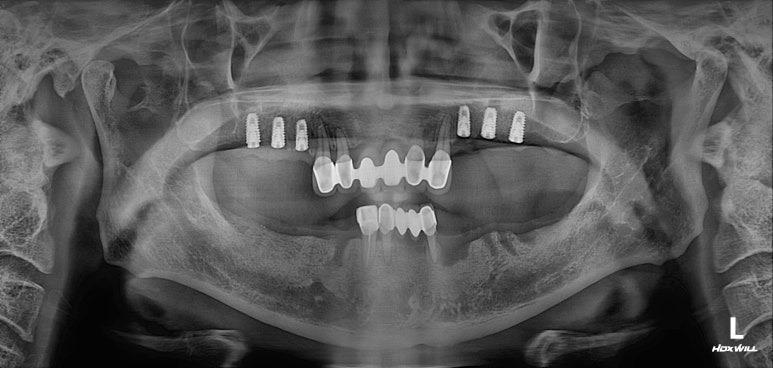

양쪽 위 어금니 부위에 깔끔하게 3개씩 임플란트를 심어드렸습니다.

이 3개의 임플란트는 시간이 흘러 첫번째, 두번째 작은 어금니 그리고 첫번째 큰 어금니가 됩니다.

치과용 파노라마 사진 상에서 잘 확인하기 어려우실 수 있지만,

화살표로 표시해둔 곳까지 측방접근법 상악동 뼈이식술이 성공적으로 잘 된 것을 확인할 수 있습니다.